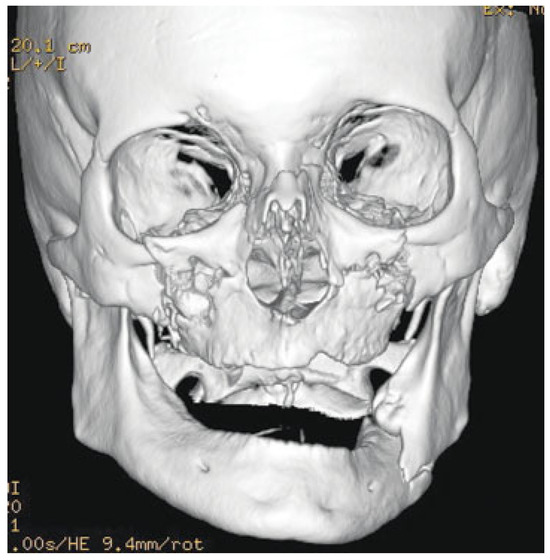

A Novel Technique for Attaining Maxillomandibular Fixation in the Edentulous Mandible Fracture

:Case Report